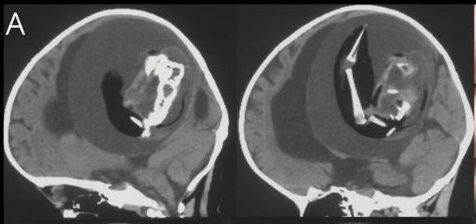

당초 아이는 대두증과 운동 능력 상실을 이유로 부모와 함께 병원을 방문했다. 의료진은 아이 머리에 단순 종양이 있다고 판단해 CT(컴퓨터 단층 촬영)를 찍었다. 하지만 의료진 예상과 정반대의 결과가 나왔다. 아이 두개골에서 태아가 발견된 것이다.

두개골 속 태아는 웅크린 채 뇌를 짓누르고 있었다. 아이와 연결된 혈관으로부터 양분을 공급받아 뼈와 팔, 손까지 발달한 상태였다. 아이는 두개골에 자리를 차지하고 있는 태아로 인해 뇌 일부분에 척수액이 고이는 수두증(물뇌증)을 앓고 있었다.

의료진은 즉시 기생 태아를 두개골에서 제거했다. DNA 분석 결과 해당 태아는 아이의 쌍둥이였던 것으로 조사됐다. 도태돼야 하는 분리된 수정란이 전뇌로 발달하면서 이 같은 사례가 발생한 것이다.